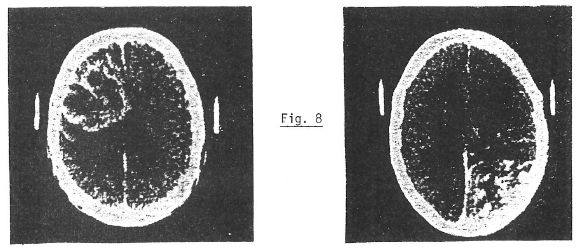

Utilisant un calculateur pour la reconstitution de la coupe, une évolution, déjà en application courante, a consisté à la reconstitution de portions d’image dans les plans frontal et sagittal, partant d’une « pile » de coupes axiales transverses. Nous avons alors un système permettant l’analyse, dans les 3 dimensions et l’on comprend pourquoi cette méthode fut qualifiée de révolutionnaire par le corps médical (fig. 7-8).

Fig. 7

Fig. 20. UNE IMAGE DE RMN donne plus de renseignements sur les tissus lésés qu’une image par tomographie aux rayons X, comme on le voit sur ces deux coupes transversales du cerveau d’un patient atteint d’une tumeur cérébrale. Sur l’image de RMN (à gauche), obtenue à partir de données en trois dimensions, la tumeur est la zone circulaire sombre du côté droit du cerveau. Sur l’image obtenue par tomographie (à droite), la tumeur n’apparaît pas. Ces images, réalisées à l’Hôpital Central du Massachussetts, sont reproduites avec l’autorisation du Journal of Computerized Axial Tomography.